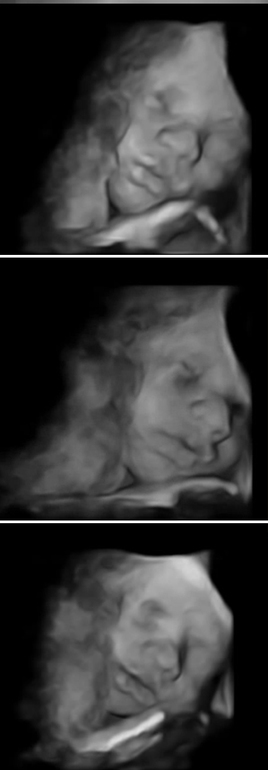

У нас ребенок одной щекой лежал на плаценте и мирно спал. Помогла маленькая шоколадка, благодаря ей он проснулся и все узи нам улыбался, это невероятные ощущения!

Показываю что у нас получилось, срок 27 недель и 3 дня

Такие полные губы =D Интересно еще то, что у всех детей в 3d крупноват нос, не знаю с чем это связанно, может быть кто-то еще замечал?

А это улыбка и приоткрытый глаз =D